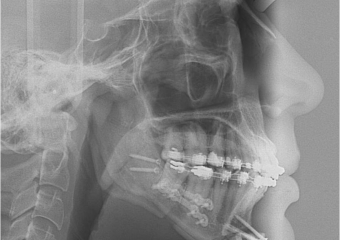

Raio x inicial

Telerradiografia inicial